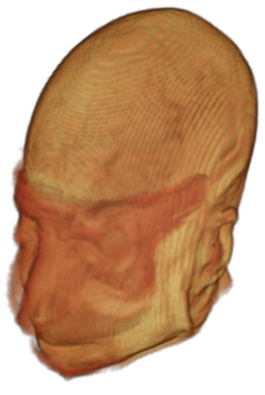

To prevent these types of attack, medical scans are currently de-identified using crude removal-based techniques [Bischoff-Grethe et al.(2007)Bischoff-Grethe, Ozyurt, Busa, Quinn, Fennema-Notestine, Clark, Morris, Bondi, Jernigan, Dale, Brown, and Fischl, Schimke et al.(2011)Schimke, Kuehler, and Hale, Milchenko and Marcus(2013)] which seek to remove privacy-sensitive parts of the head (examples in Figure 3). However, as we demonstrate, these existing techniques fail to reliably hide the patient’s identity – or they are so aggressive that they impair further medical analyses. A better solution is needed.

Benchmark De-Identification Methods. We compare our result with three publicly available and widely-established methods for de-identification of MRI head scans, depicted in Figure 3. All methods have in common that they (1) are not deep-learning-driven, (2) require no additional training and (3), are used on a day-to-day basis in neuroscience and clinical research. All procedures were applied with default settings on images of resolution . The methods include QUICKSHEAR [Schimke et al.(2011)Schimke, Kuehler, and Hale], FACE MASK [Milchenko and Marcus(2013)], and DEFACE [Bischoff-Grethe et al.(2007)Bischoff-Grethe, Ozyurt, Busa, Quinn, Fennema-Notestine, Clark, Morris, Bondi, Jernigan, Dale, Brown, and Fischl]. Descriptions of the methods are provided in the Appendix. We also include MRI WATERSHED [Ségonne et al.(2004)Ségonne, Dale, Busa, Glessner, Salat, Hahn, and Fischl], a skull-stripping method that removes everything except the brain.

A handful of de-identification techniques exist for MRI scans, which are conventionally used for sharing and distribution of MRI data. These existing methods rely on a removal approach to privacy. DEFACE [Bischoff-Grethe et al.(2007)Bischoff-Grethe, Ozyurt, Busa, Quinn, Fennema-Notestine, Clark, Morris, Bondi, Jernigan, Dale, Brown, and Fischl] estimates the probabilities of voxels belonging to the face based on an atlas of healthy control subjects. The scan is de-identified by setting intensities of voxels whose probabilities are small enough to zero. QUICKSHEAR [Schimke et al.(2011)Schimke, Kuehler, and Hale] is a fast but simple approach that computes a hyperplane to divide the MRI into two regions: one containing facial structures, and the other containing the brain of the scan. Voxels in the first part are set to zero. FACE MASK [Milchenko and Marcus(2013)] uses a filtering method to blur the facial features. These existing de-identification approaches are based on traditional computer vision techniques; we believe that the proposed algorithm is the first to adopt a learning-based approach.